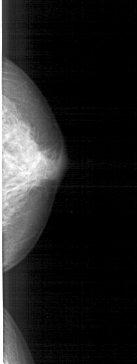

A_1867_1.LEFT_CC

LEFT_CC LINES 4261 PIXELS_PER_LINE 1651 BITS_PER_PIXEL 12 RESOLUTION 43.5 NON_OVERLAY